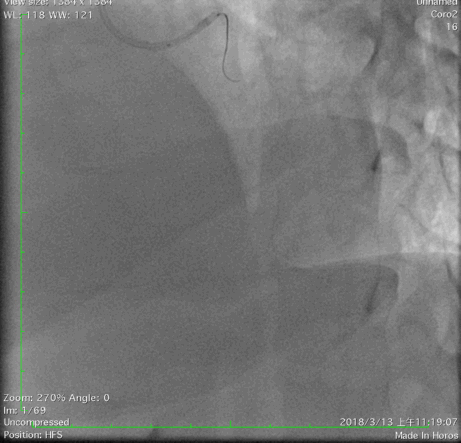

2018年3月13日外院行造影检查示左优势,LAD发出后闭塞,LCX优势型,远端可见与LAD远端形成心外膜侧支,OM1闭塞,RCA闭塞。当地尝试开通RCA和LAD失败,经我院心内、外科联合讨论后,拟心内科介入开通LAD闭塞。

冠脉造影:

右足

右头

蜘蛛位

左头